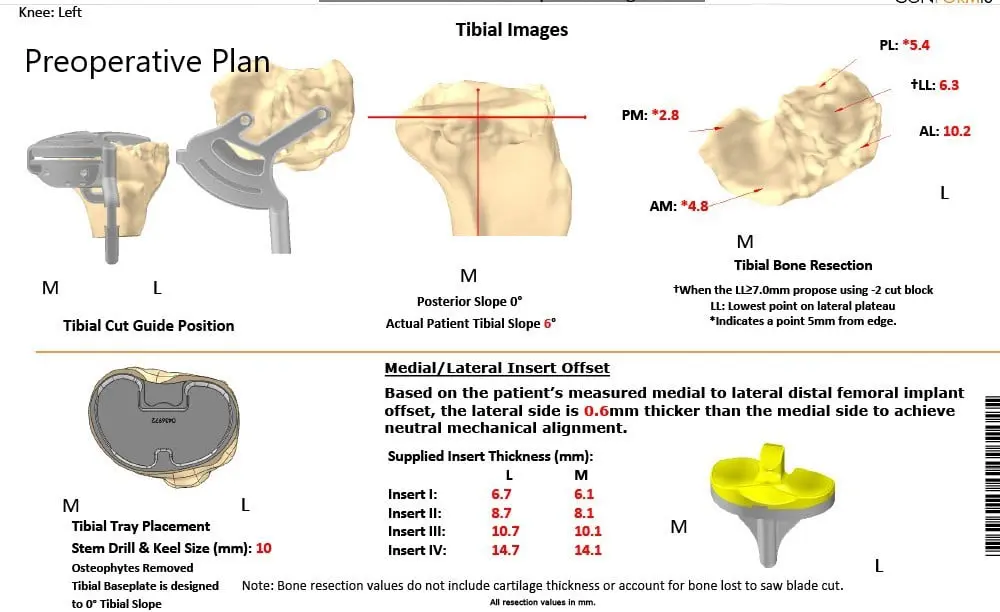

The patient underwent a CT scan 3 weeks prior to the procedure. A preoperative plan was formulated based on the patient’s anatomy and biomechanics. The plan outlined the bone cuts for maximum bone preservation and accurate duplication of natural knee biomechanics. The CT scan images were used to construct custom implants and instruments uniquely designed for the patient.

Complete Orthopedics patient-specific surgical plan for customized total knee replacement in a 59-year-old male.